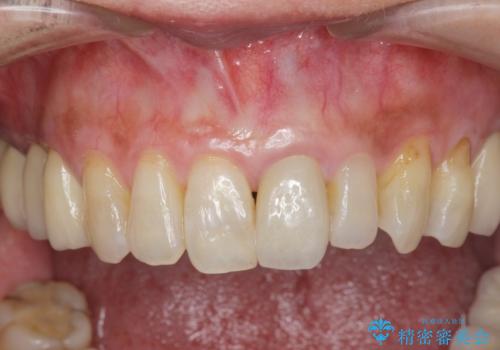

前歯の変色 セラミッククラウンによる審美回復

- 前歯の変色による審美障害の改善を希望され来院されました。

ジルコニアクラウンによる審美性の改善を計画します。

神経の治療をした歯は時間の経過と共に色調の変化が見られます。

このような際、ジルコニアクラウンを装着することで審美性の改善を達成することができます。